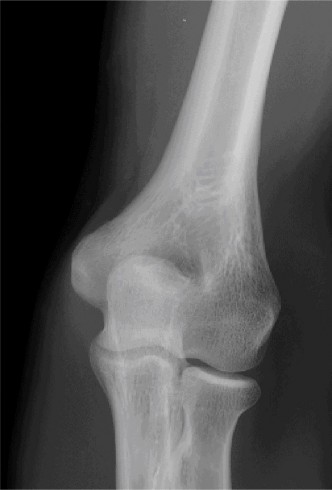

Understand the operative treatment of SC joint osteoarthritis and the important structures to preserve? CASE 29 Dr. Robert J. Stewart A 57-year-old, right-hand-dominant female presents with left shoulder pain and stiffness for the last 3 months. She has a history of diabetes, hypothyroidism, and breast cancer. She reports having difficulty sleeping on her left side. She localizes her pain over the deltoid insertion. The stiffness has become worse. The pain has been improving over the last 3 weeks but is exacerbated by extreme left shoulder motion. She is having difficulty dressing and combing her hair. She works as a statistical analyst and sits at a desk most of the day. On physical examination, she has normal strength with left shoulder abduction and external rotation, a negative cross-body adduction test, and no pain with a supinated O’Brien’s test. An x-ray is obtained and shown in Figure 2–76.

Figure 2–76

The correct answer is (D). Adhesive capsulitis (AC) is a specific pathologic entity that produces subsynovial chronic inflammation resulting in capsular thickening, fibrosis, and adherence of the capsule to itself and the anatomic neck of the humerus. The thickened and stiff capsule causes pain and a restraint to motion. This is called primary, or idiopathic, AC. The remaining answer choices are incorrect and can result in symptoms similar to those of AC (i.e., loss of shoulder motion and pain), but their underlying etiology is different. It is important to recognize that all these conditions can cause a stiff and painful shoulder (a “frozen shoulder”) but is not necessarily AC. AC occurs more frequently in sedentary females in the non-dominant hand, and has been associated with diabetes mellitus, thyroid dysfunction, breast cancer treatment, cardiovascular disease and cerebrovascular disease.

The patient is diagnosed with stage 3 adhesive capsulitis. On physical

examination, which of the following is the most likely to be found?

- Decreased passive and active range of motion of the shoulder in all planes